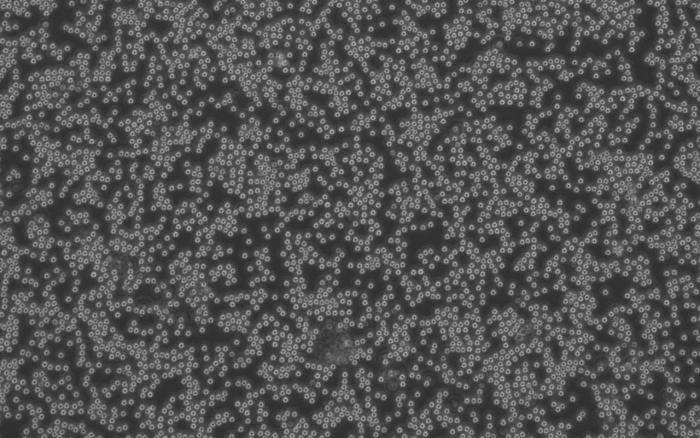

وباستخدام التحرير الجيني، أظهر العلماء أن ETS2 كان ضرورياً لجميع الوظائف الالتهابية تقريباً في الخلايا البلعمية، بما في ذلك العديد من الوظائف التي تساهم بشكل مباشر في تلف الأنسجة في مرض التهاب الأمعاء، ومن المثير للدهشة أن زيادة كمية ETS2 في الخلايا البلعمية أثناء الراحة حولتها إلى خلايا التهابية تشبه إلى حد كبير تلك الموجودة في مرضى التهاب الأمعاء.